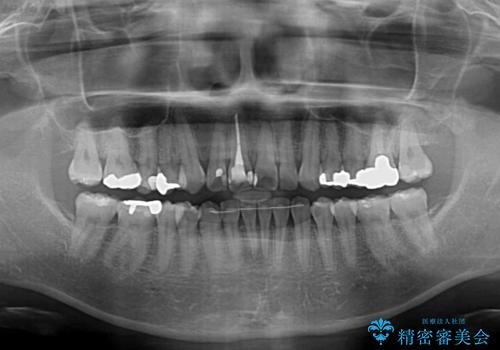

- 前歯のデコボコを治したいとのことで来院された患者様です。

上下顎ともに歯列全体の後方移動とIPR(歯と歯の間を削る)によってデコボコが解消するように設計し、インビザラインにより治療を行うこととしました。

しっかりと装着時間を守ってくださったのですが、途中妊娠にともなう悪阻や出産といったイベントがあり、予定よりも治療期間が長くなりました。